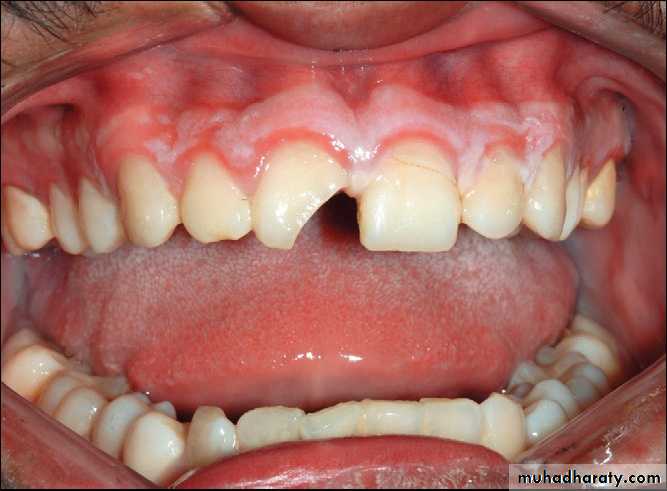

Primary contact in premolar region indicating an alveolar process fracture in the maxilla.